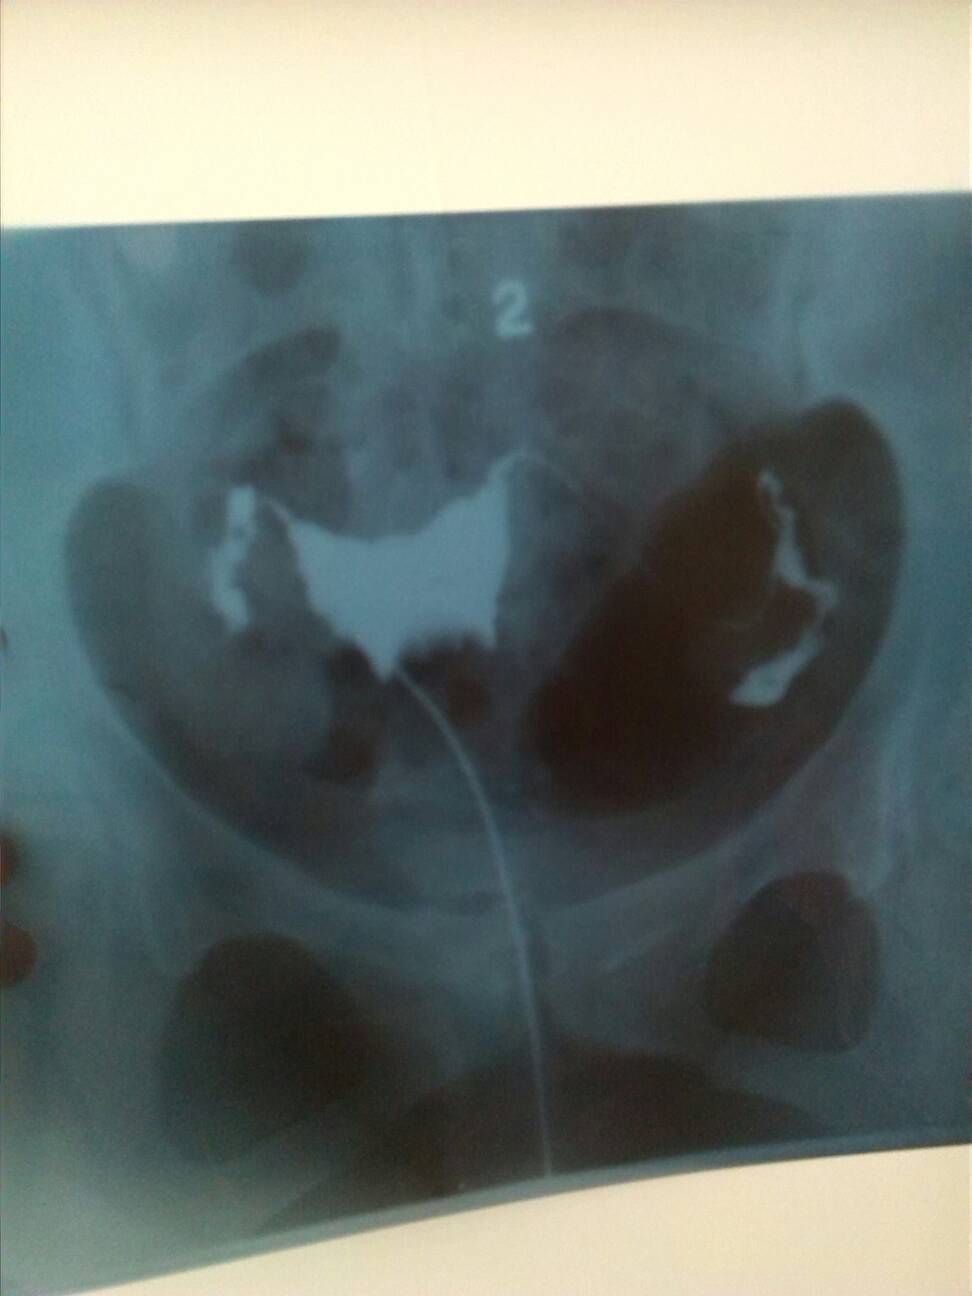

想要怀孕,做了输卵管造影术,结果有两种说法,看病人的医生说右边通畅,左边通而不畅;照片子的医生说左 想要怀孕,做了输卵管造影术,结果有两种说法,看病人的医生说右边通畅,左边通而不畅;照片子的医生说左边通畅,右边通而不畅。听谁的啊,有会看片子的医生帮忙看一下啊? 点击展开 兜兜滴麻麻 2014-05-17 13:11 为您推荐: 其他回答 病情分析: 以前有没有过怀孕的情况? 指导意见: 从图上看两侧的输卵管都有点不畅建议进行详细的检查及治疗。 匿名用户 2014-05-17 15:15 相关问题 输卵管造影后医生说没什么大问题,就是左边欠通畅 需要治疗吗 医生,我怀孕5个月,为什么最近肾很痛,一下右一下左边,宝宝在里面老是动来动去 怀孕快三个月了,刚刚子宫左边痛了半个多小时,赶去医院又不痛了,医生让做B超,没做又回家了